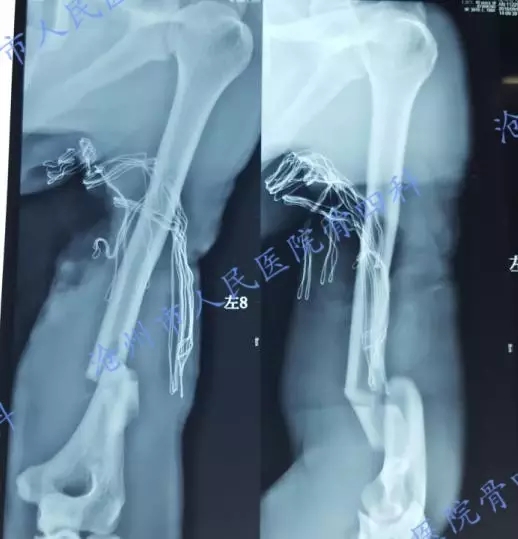

辅助检查:

完善各项术前准备后,立即行左上肢清创、肱骨骨折内固定、血管移植吻合,创面VSD覆盖术。

术中见肱动脉断裂缺损约15cm,无法直接吻合,取头静脉桥接。(术前检查左上肢尺桡动脉搏动消失,修复吻合血管后,尺桡动脉恢复搏动)

术中见尺神经、正中神经断裂缺损约17cm,予清创后二期修复。为能尽快恢复患肢血运,左肱骨远端骨折临时应用2枚螺钉固定。